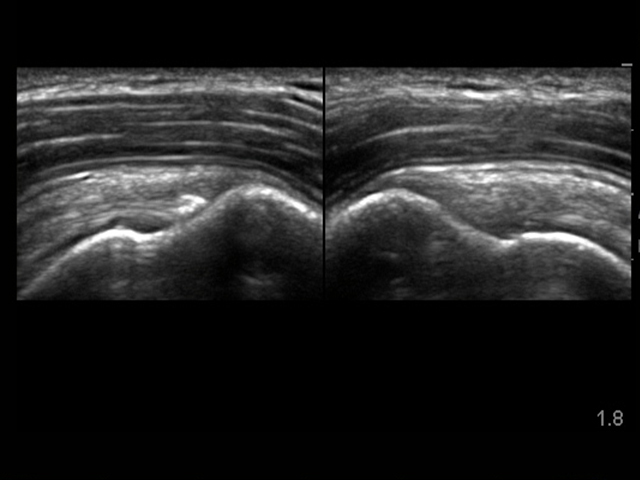

肩棘上筋石灰化病変の画像